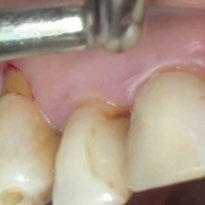

y lo que se pudo preservar del hueso malar. Se añadió una malla sinterizada infraorbitaria para dar volumen a la mejilla y se planificaron dos brazos de conexión que emergieran en las posiciones 24 y 26 de forma subgingival (Figuras 8 y 9). La superficie interna que apoyaba en el hueso era de titanio microrrugoso, y la superficie externa y conectores de titanio pulido y hexágono externo universal (Figuras 10 y 11). La cirugía se hizo bajo anestesia general en infiltración con anestesia local (4% articaína, 1:100.00 epinefrina), levantando el

colgajo cutáneo de la mejilla por vía intraoral, preservando el colgajo temporal para no comunicar con el remanente de la cavidad naso maxilar (Figura 12). Se emplearon 10 tornillos de osteosíntesis de 1,9 mm y la estabilidad primaria obtenida fue excelente (Figura 13)

4 meses después de la cirugía la encía estaba completamente cicatrizada y las conexiones de los implantes tipo hexágono externo universal quedaron a nivel yuxtamucoso. En este caso no se requirió el empleo de pilares transepiteliales y las impresiones fueron tomadas